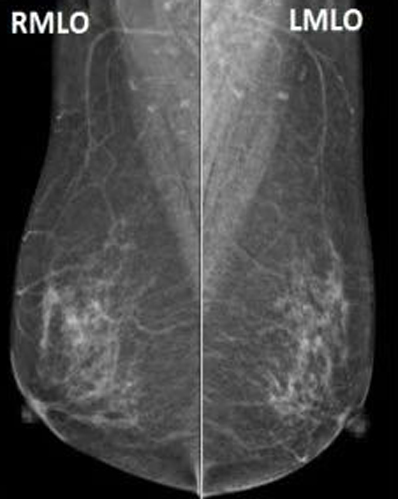

经调试已正式投入临床使用,该设备作为新一代数字化二维乳腺机,配备了双焦点高速X射线管组件,非晶硅高分辨率平板探测器,低剂量钨靶球管降低辐射剂量。可以提供高质量的检查图像,并且可根据需要调整图像的对比度和亮度,有助于致密乳腺高清成像,提升早期病灶检出率 ,高效助力乳腺疾病早筛早诊;依托智能压迫系统自动调整压迫力,保证受检者舒适体验,用心关爱乳腺健康,成就致密乳腺优质成像。

乳腺钼靶,全称乳腺钼靶X线摄影检查,是一种低剂量乳腺X线拍摄乳房的技术,是目前诊断乳腺疾病的首选和最简便、最可靠的无创性检测手段。留取的图像可供前后对比,不受年龄、体形的限制,目前已作为常规的检查。它能清晰显示乳腺各层组织,可以发现乳腺增生、包块、钙化及各种乳腺良恶性肿瘤,可观察到小于0.1毫米的微小钙化点及钙化簇,是早期发现、诊断乳腺癌的最有效和可靠的检查方法。